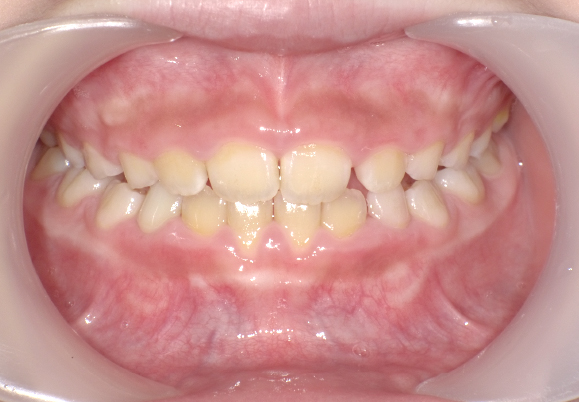

治療内容 治療内容:親御さんよりお子さんの歯並びが気になっていた。特に前歯の重なりを気になっていた。また、お母さん自身も歯並びの治療を行った経験があり、今回は早い段階での治療を行いました。現在は治療途中でありますが、前歯の重なりは早期で改善され、これからは下の歯を綺麗に並べていく予定となっています。

症例写真 2020.11~ 精密検査を実施(相談時は7歳)

2021.1~ マイオをセット、治療開始

2021.11 現在、治療7割程度完了、残り治療期間1年程度を予定

2020.11

2021.10